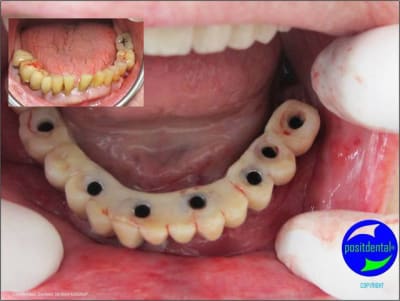

06/05/2011 à 11h02

3D maxillaire inférieur et photo